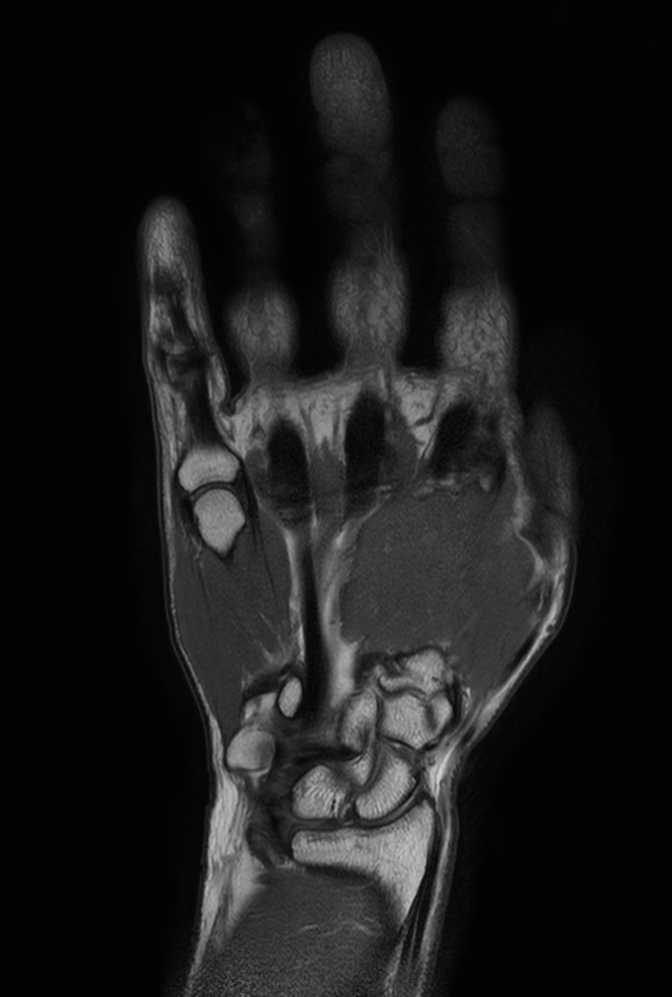

Coronal T1w TSE mDIXON XD (In Phase)